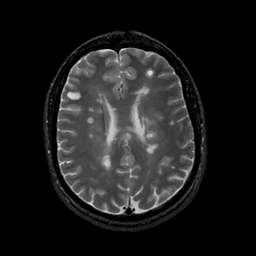

MR Study #11, May 5, 1991 -- Slice #32